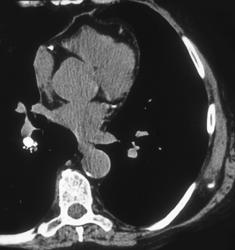

Small Cell Lung Cancer With Left Upper Lobe Collapse